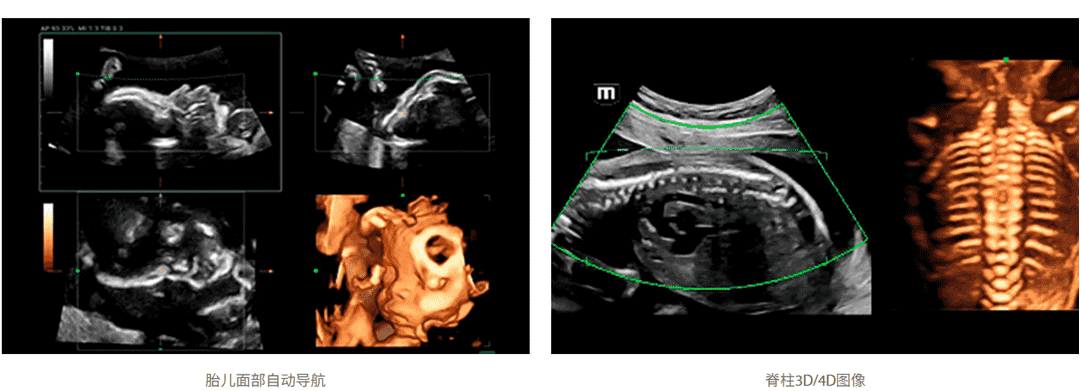

针对胎儿颅脑、面部、脊柱、长骨这类具备3D特性化的操作的临床应用场景,仁合创新开发了场景化自动容积扫描,只需“一键”即可完成自动场景识别、自动成像及优化、自动切面获取、自动定量分析,真正实现了贯穿整个检查流程的自动化工作流,降低诊断对操作者的依赖性,轻松提升病人检查效率。